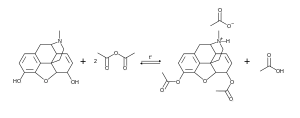

Se obtiene mediante un proceso de acetilación de la morfina[53]

La materia prima para uso industrial o de laboratorio durante la síntesis de la heroína es la morfina. La acetilación con anhídrido acético o cloruro de acetilo se produce durante el calentamiento. No es necesario un exceso de cloruro de acetilo, ya que en este caso, el resultado, cloruro de hidrógeno, se une a la parte básica de nitrógeno núcleo morfinanovogo, y parcialmente retirado de la mezcla de gas que desplaza el equilibrio casi por completo hacia la formación de derivados diacetilados. El crudo de la acetilación se purifica por adición de carbón activo y filtrado para ser posteriormente recristalizado en etanol.

El rendimiento de la reacción es de hasta del 95,5%.[54]

Los reactivos acetilantes están incluidos en la lista de precursores de estupefacientes y el tráfico en muchos países está limitado y controlado en conformidad con la ley y los tratados internacionales.[55]